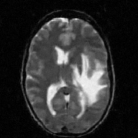

The reconstructions of a 256×256256256256\times 256 brain image from its radial samples acquired with a 40 spoke trajectory are shown in Fig. 6. The measurements are corrupted with zero mean complex Gaussian noise of standard deviation σ=18.8𝜎18.8\sigma=18.8. All methods result in loss of subtle image features since the acceleration factor and the noise level are high. We observe that the NLS scheme provides better recovery than the competing methods. The quantitative results in this setting for various MR images are shown in the bottom section of Table IV. We observe that the SNR improvement offered by NLS over the other methods are not as high as in the previous cases, mainly due to the considerable noise in the data and the high acceleration.

Figure 6: Comparison of the algorithms in the presence of noise. We consider the recovery of a 256×256256256256\times 256 original MRI brain image from its radial trajectory with 40 spokes, contaminated by Gaussian noise with standard deviation σ=18.8𝜎18.8\sigma=18.8. The error images are magnified by a scale of 5 fold for the best visibility. This is a challenging case due to the high undersampling factor and high measurement noise. We observe that the NLS scheme provides the best overall reconstructions.